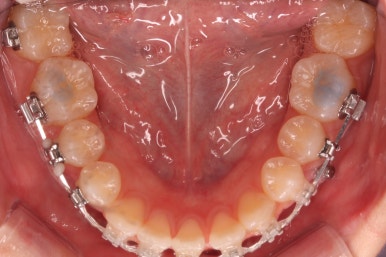

부산교정 키다리아저씨치과에 처음 내원하셨을 때의 입안 모습입니다.

윗니가 삐뚤어져 있고, 아래앞니 사이에는 틈이 듬성듬성 보입니다.

아랫니를 살펴보면 화살표 표시를 해둔 송곳니~송곳니 사이에 치아가 1개 모자랍니다. 원래는 4개의 앞니가 있어야 하는데, 3개 밖에 없었습니다. 이런 결손치아의 경우는 다음과 같은 문제가 생깁니다.

결손치아 부위에 틈이 생깁니다.

결손치아 주위 치아들이 제대로 서있지 못하고 기울어지게 됩니다.

위-아래 짝이 맞지 않아 중앙선이라든지 교합에 문제가 생깁니다.

이번의 경우 앞니가 하나 없는 경우여서 위-아래 앞니가 앞뒤로 간격이 멀어지게 됩니다.